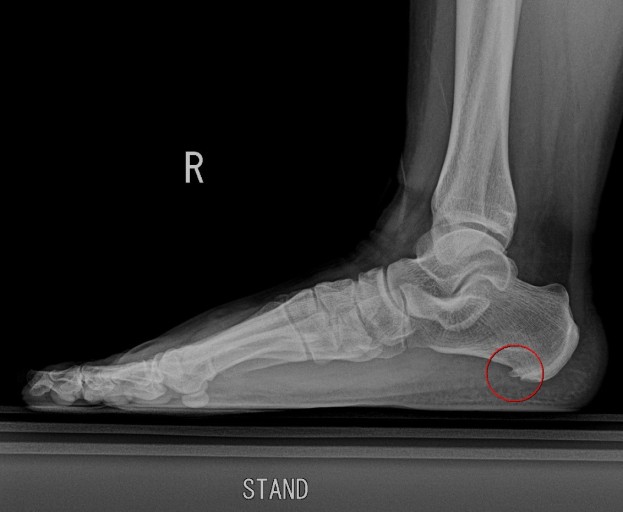

말로만 듣던 족저근막염에 걸렸다

어느순간 집안에서 걸어다니기만 해도 발뒷꿈치에 통증이 느껴지기 시작했다. 말로만 들어왔던 족저근막염에 걸린것이다. 통증이 심해서 발 뒷꿈치를 들고 걸어다녔고, 회사에서는 그동안 사용하던 얇은 슬리퍼를 갖다버렸다.

족저근막염은 우리 발바닥에 있는 족저근막 이라는 조직이 염증을 일으켜서 발생되는 병인데, 이 족저근막이 발바닥을 지탱하고 걸음걸이를 안정화 시키는 역할을 한다. 이 조직에 과도한 스트레스가 가해지면 염증이 생기고, 이게 바로 족저근막염이다.